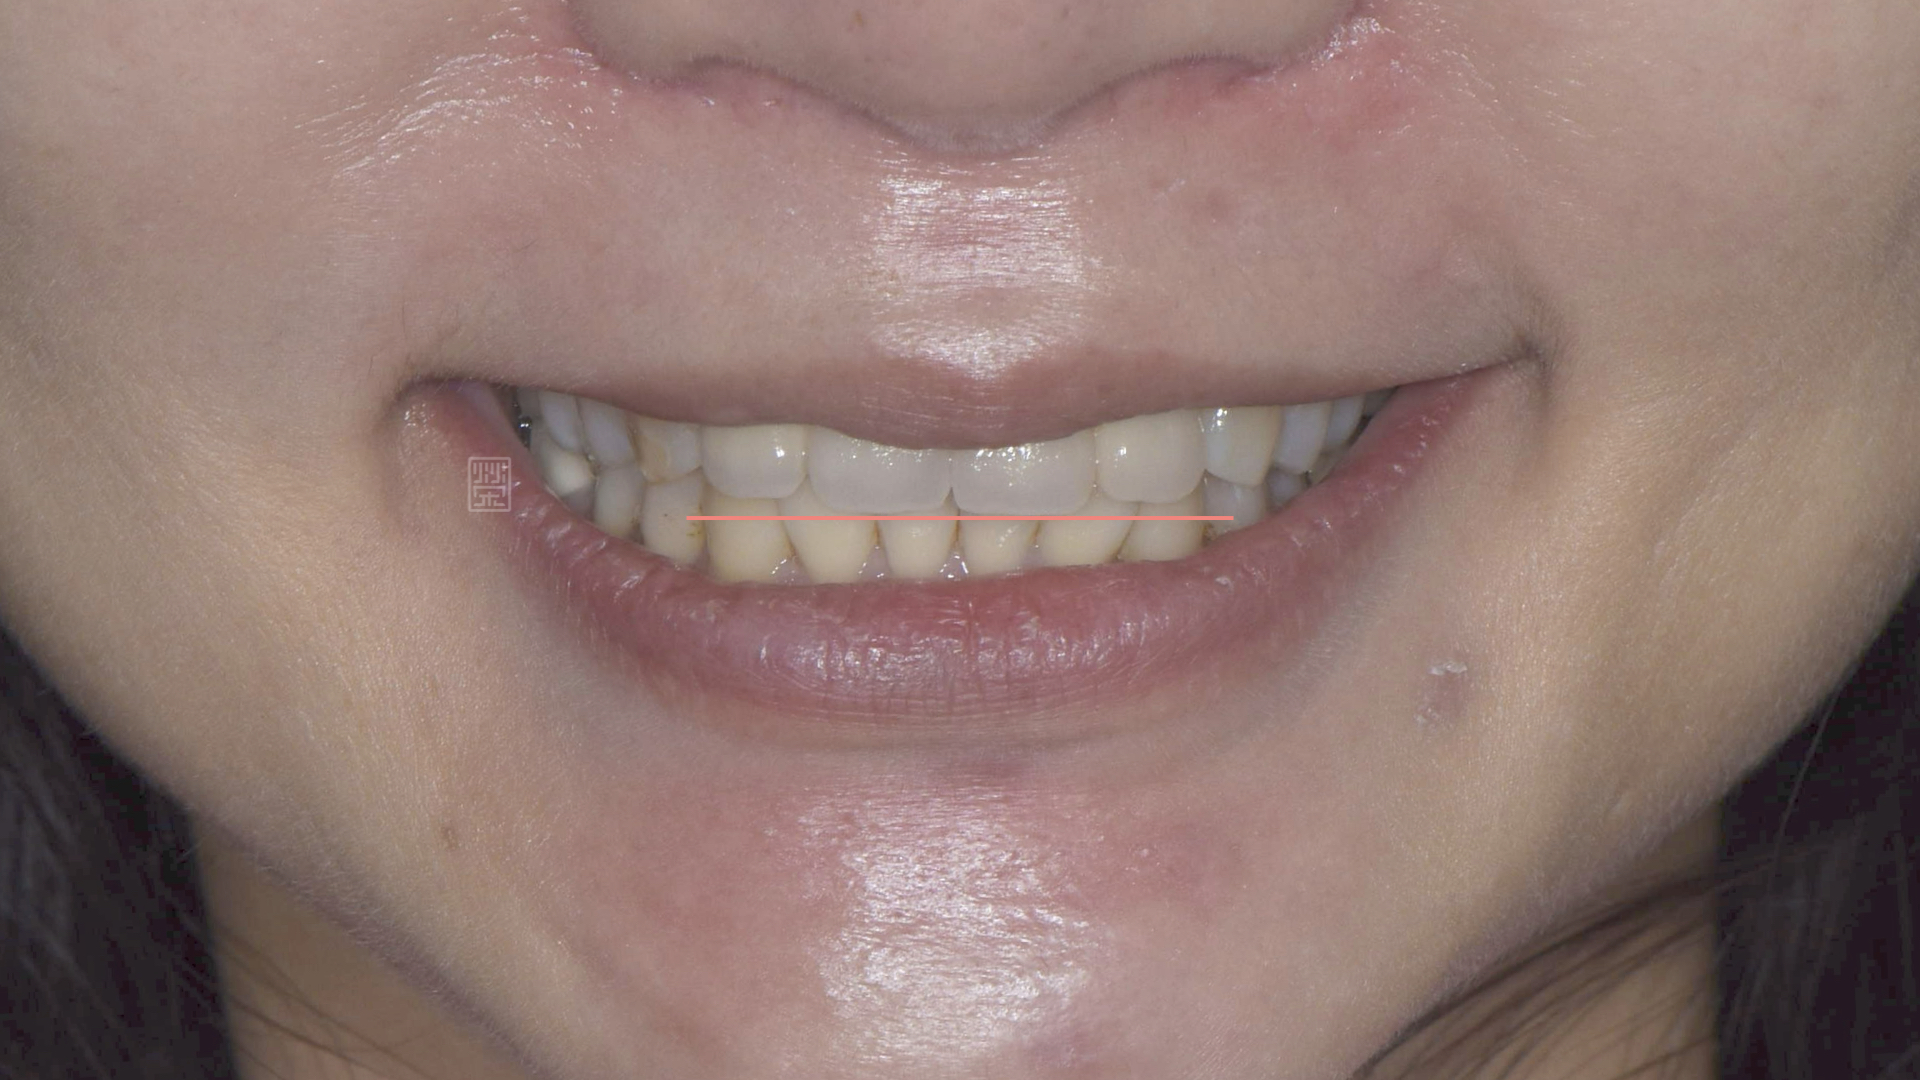

與高小姐討論後,榮醫師建議將門齒長度增加,讓門牙切端的弧形連線與下唇弧形線平行,也就是我們常說的微笑曲線,搭配和諧的顏色,讓高小姐的笑容充滿精神。

和諧燦爛的笑容